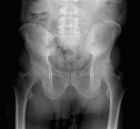

D.R. - 65 year old male, c/o worsening right hip/buttock pain for six months. Pain is constant, worse with activity. Tylenol helps a bit. No F/C or constitutional sx.

PMH: Crohn's disease, nephrolithiasis, prostate infection, gallstones

Zoom image: Radiological image Radiological image.